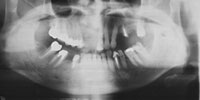

吉本歯科医院においては、口内写真とパノラマレントゲンを撮影し、まずは顎の骨の状態まで詳しく確認しました。

噛み合わせが非常に悪く、上の歯が下の歯にすっぽりと覆いかぶさっておりまともに噛めていない状態であることがわかりました。.

・歯を支える骨も溶けて薄くなってしまっている状態